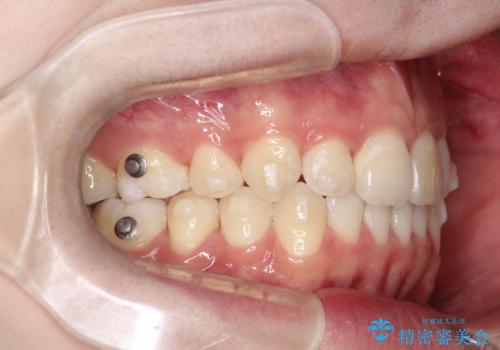

- 矯正装置

- 審美装置

- 患者様は、歯並びのガタガタ(重度の叢生)を改善したいとのことで来院されました。診察すると、歯列のスペース不足が著しく、前歯が重なり合い、噛み合わせにも影響が出ている状態でした。歯をきれいに並べるためには抜歯によるスペース確保が不可欠と判断し、上下の小臼歯4本を抜歯したうえで、目立ちにくい審美ワイヤー矯正(白いワイヤーと透明ブラケット)を用いた治療計画を立てました。

抜歯によって歯を動かすためのスペースを確保。その後、審美ワイヤー矯正を用いて歯を1本ずつ適切な位置に誘導しながら、噛み合わせのバランスも整えていきました。時間はかかりましたが、ガタガタの歯並びがきれいに整い、機能的にも審美的にも満足のいく仕上がりとなりました。患者様からは「歯並びが劇的に改善し、見た目だけでなく噛みやすさも向上した」と喜びの声をいただきました。